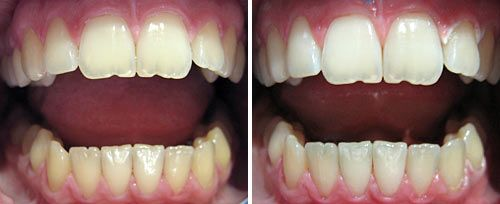

牙齿美白

牙齿美白:漂白凝胶中的水分吸收激光能量后,产热并催化过氧化氢漂白成分与牙釉质表面的反应,且热量不会深度穿透,不损伤牙本质和牙髓组织。

口腔激光怎么治疗口腔特色诊疗——激光治疗_https://www.jmylbn.com_新闻资讯_第8张

激光牙齿美白前后对比图